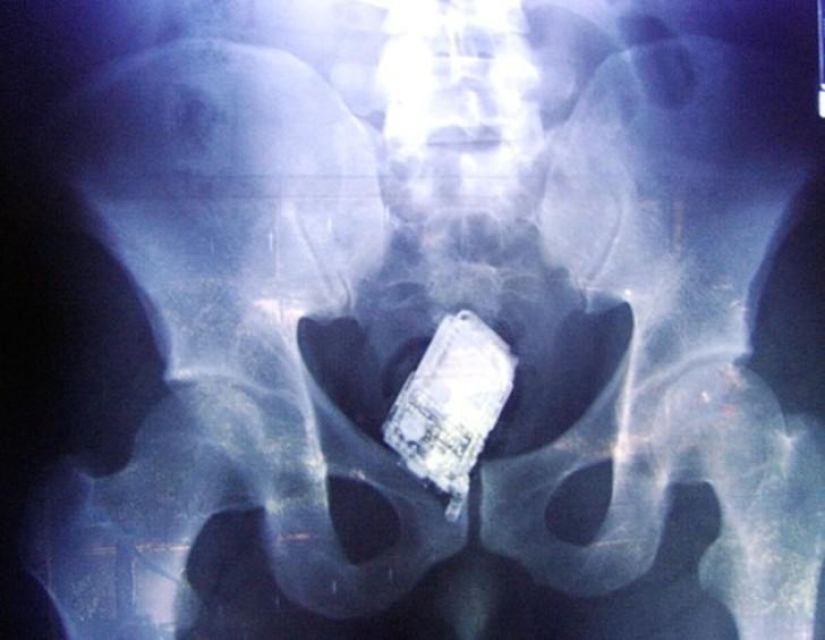

Teléfono móvil.